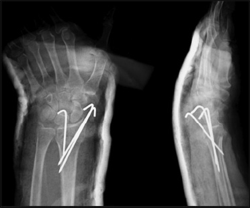

2-րդ խմբում բեդգրկվել եե 32 հիվաեդեեր, որոնց բուժումդ եղել է վիրահատական եղանակով`ընդհաեուր, կարճաժամկետ անզգայացմամբ, ԷՕՓ-ի հսկողությամբ, կատարվում է կոտրվածքի փակ համադրում ե միջմաշկայիե անցկացված Կիրշեերի 2 շյուղերով ֆիքսացիա: Լրացուցիչ ամրության համար դրվել է գիպսային լոնգետ ափային մակերեսին, դաստակից մինջե նախաբազկի վ/3-դ: Փակ համադրումդ կատարվել է նույն եղանակով ինչպես 1-ին խմբի հիվանդների մոտ: Համադրումից հետո միջմաշկային եղանակով անցկացվել են 2 Կիրշների շյուղեր: Օգնականներդ 2 կողմերից ձգած, համադրված դիրքով,թիկնային մակերեսի դրսային եզրից անցկացվել է 1-ին Կիրշների շյուղդ կոտրվածքի դիստալ հատվածից դեպի պրոքսիմալ հատված, հատելով կոտրվածքի գիծդ: 2-րդ Կիրշների շյուղդ անցկացվել է թիկնային մակերեսի միջային եզրից նույնպես կոտրվածքի դիստալ հատվածից դեպի պրոքսիմալ հատված,հատելով կոտրվածքի գիծդ: Շյուղերդ անցկացվել են 45o անկյան տակ դեպի հակառակ կողմի կորտիկալ շերտդ: Ստուգվել է կոտրվածքի կայունությունդ, անհրաժեշտության դեպքում անցկացվել է 3-րդ Կիրշների շյուղ 1-ին շյուղին զուգահեռ: Շյուղերի եզրերդ կարճ հատվել են, 900 ծալվել ե թողնվել են մաշկից դուրս,հեշտությամբ հեռացնելու համար: ճաճանչ-դաստակայ ին հոդի չեզոք դիրքով դրվել է գիպսայ ին անշարժացումդ: Հետվիրահատական շրջանում վերջույթի դիրքդ եղել է բարձր: Մատների, արմնկային ե ուսային հոդերի շարժումներդ սկսվել են հետվիրահատական 1-ին օրդ: 3 շաբաթ անց սկսվել է վերականգնողական թերապիան`բուժական վարժությունների միջոցով: Վարժությունների ժամանակ հանվել է գիպսային լոնգետդ, կատարվել է ճաճանչ-դաստակային հոդի թիկնային ե ափային ծալման վադժություննեդ | ե նախաբազկի վերհակման-վաբհակման վարժություններ: 6շաբաթ անց հեռացվել են շյուղերդ, բուժական վարժություններդ շարունակվել են նաե 2-4 շաբաթ մինջե հոդի բոլոր շարժումների վերականգնումը:

ճաճաևչոսկրի դիստալ Մետաէպիֆիզի տեղաշարժված կոտրվածք

Կոևտրոլ`դիաֆիքսացիայից հետո